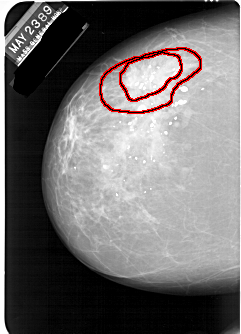

A_1247_1.LEFT_CC

LEFT_CC LINES 6331 PIXELS_PER_LINE 4576 BITS_PER_PIXEL 12 RESOLUTION 43.5 OVERLAY

LEFT_MLO LINES 6226 PIXELS_PER_LINE 4531 BITS_PER_PIXEL 12 RESOLUTION 43.5 OVERLAY

FILE: A_1247_1.LEFT_CC.OVERLAY

TOTAL_ABNORMALITIES 1

ABNORMALITY 1

LESION_TYPE MASS SHAPE IRREGULAR MARGINS SPICULATED

ASSESSMENT 5

SUBTLETY 5

PATHOLOGY MALIGNANT

TOTAL_OUTLINES 2

BOUNDARY

CORE